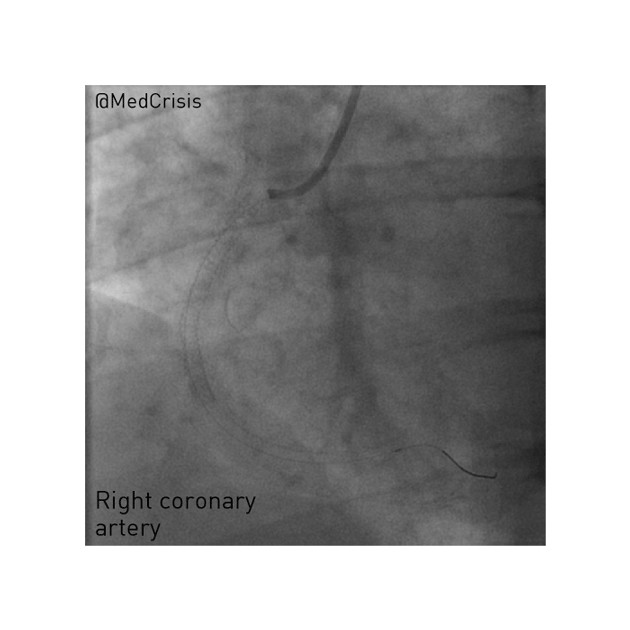

A 3.5mm wide and 38mm long drug-eluting stent was placed without complication in her RCA, producing a nice angiographic result. However, the long period of coronary occlusion may well have caused significant myocardial injury. She was kept under close observation.